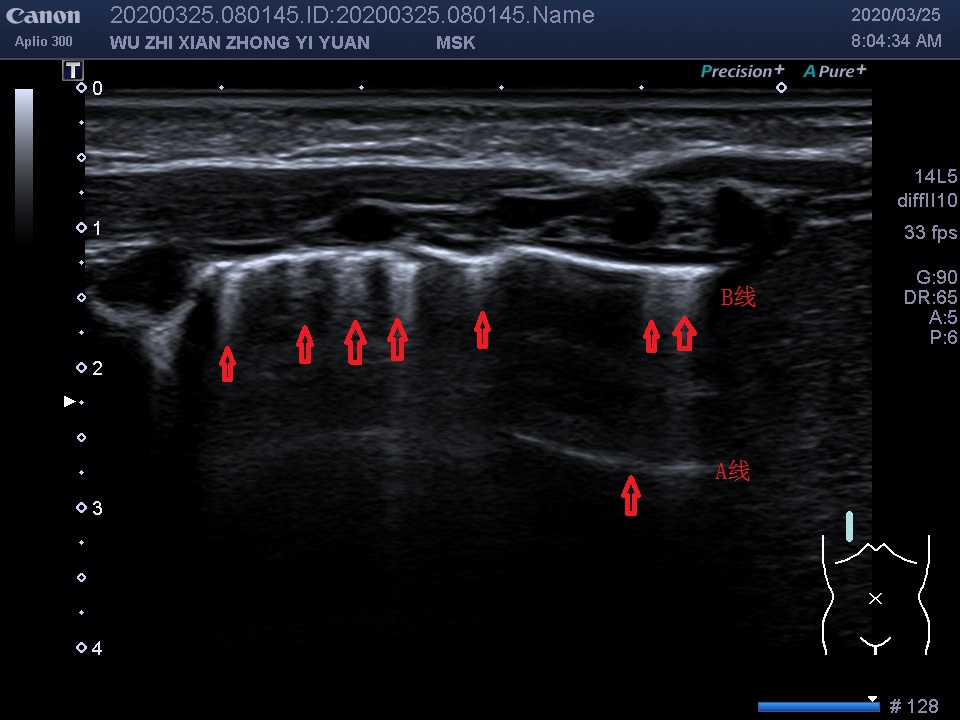

A线:因胸膜-肺界面声阻抗差异产生多重反射而形成的水平伪像,超声下呈一系列与胸膜线平行的线状高回声,位于胸膜线下方,彼此间距相等。正常肺组织至少可以见到3 条以上A线,M超下为海岸征。

B线:由于肺组织中液体量增加,导致超声波遇到肺泡气-液界面产生强烈多次反射形成的振铃效应伪像,起始于胸模线并与之垂直、呈放射状发散至肺野深部的线性高回声称为B线,反应肺含水量增加。

图中所示:红色箭头所指竖线为B线,箭头所指横线为A线,于右肺锁骨中线第2-5肋间,锁骨旁线及腋前线均可探及密集较粗大B线,部分呈“火箭征”,滑线可见,A线显示欠清晰。